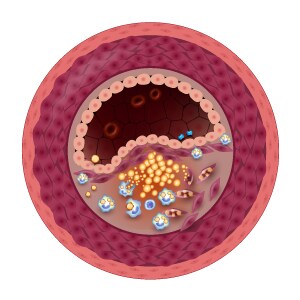

With clean and elastic blood vessels, blood, oxygen and nutrients can reach their destinations easily and quickly.

However, heart disease risk factors can cause your blood vessels to become blocked and stiff, restricting blood flow and increasing your chances of heart problems.

Unhealthy diet – Too much sugary and fatty food in your diet? Beware of high levels of LDL (“bad”) cholesterol that will build up in your arteries and clog blood vessels.

High cholesterol – The buildup of plaque in your blood vessels due to high LDL cholesterol levels increase your chances of experiencing a heart attack, stroke or artery disease.

High blood pressure – High blood pressure damages blood vessel walls, making it susceptible to cholesterol plaque formation, which can result in heart attack or stroke.